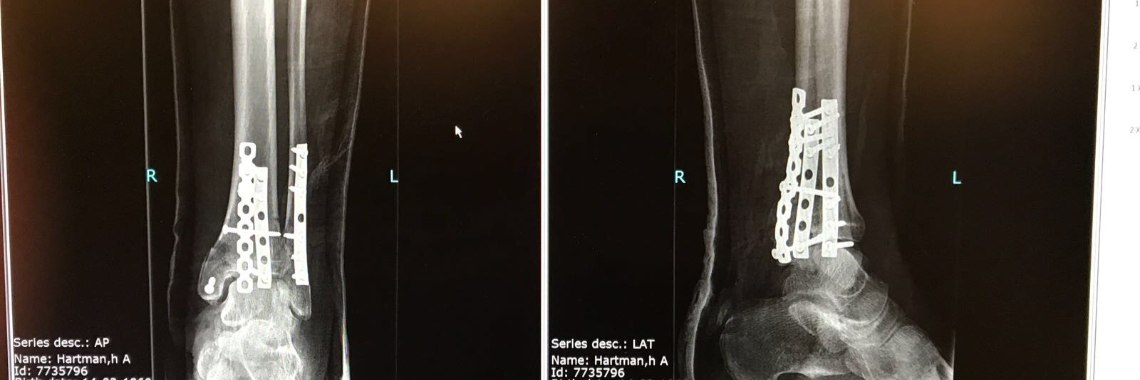

Op 5 november 2017 brak het zadel van mijn fiets spontaan af. Het gevolg was dat ik een gecompliceerde enkelfractuur opliep. Eerder heb ik daar al een blog aan gewaagd. Deze blog is een update. Wellicht zijn er mensen die ook zo'n breuk hebben opgelopen en in mijn verhaal dingen herkennen. Misschien heb je nog wel tips of suggesties, daar sta ik erg voor open.

Vanaf de dag dat ik uit het gips ben gaat het herstel moeizaam, om maar niet te zeggen erg moeizaam. Ik schrok al toen het gips eraf was, mijn voet voelde als een klomp, ongevoelig, stijf, dik en onbeweeglijk. Belasten ging aanvankelijk goed, het bot voelde stevig genoeg om op te staan. Lopen is een ander verhaal. Sommige spieren werken niet of nauwelijks mee, pas na een maand kwam ik erachter dat ik niet op mijn tenen kon staan. De weke delen (spieren, ligamenten, kapsels, aders), zo vertelde de arts, zijn ook kapot gegaan en die hebben tijd nodig om te herstellen. Het bewegen van mijn grote teen is erg moeizaam en pijnlijk bovendien.Â